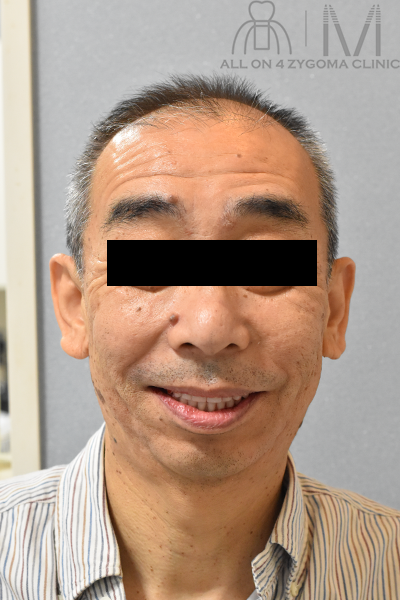

術前顔貌所見

顔貌は左右非対称、右口角の位置が左口角の位置より高位にある。鼻唇溝は深く、右側で著明。鼻翼の位置は両側ほぼ対称。

上唇が薄く、下唇が厚い。

笑顔時に上唇から見える上顎前歯部は歯冠部の1/3部が露出

バッカルコリドーは写真では認めるようだが不明瞭。